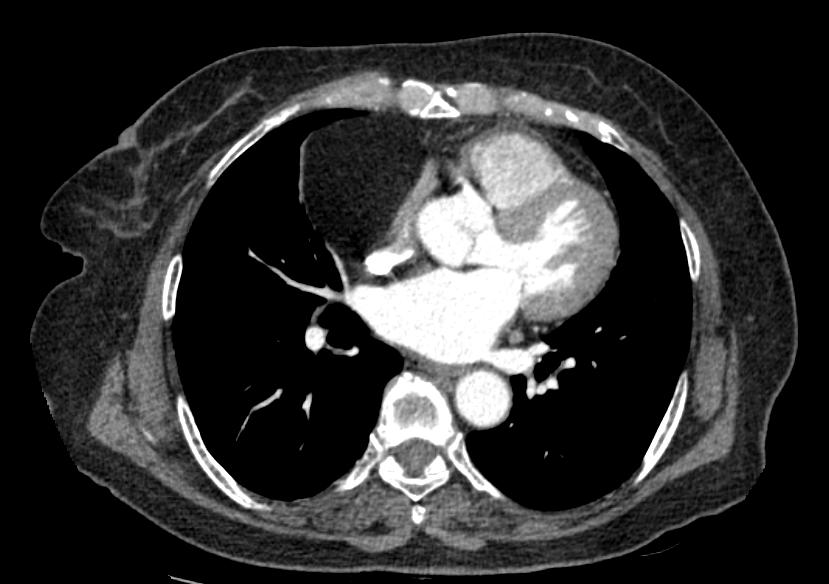

< Chest CT >